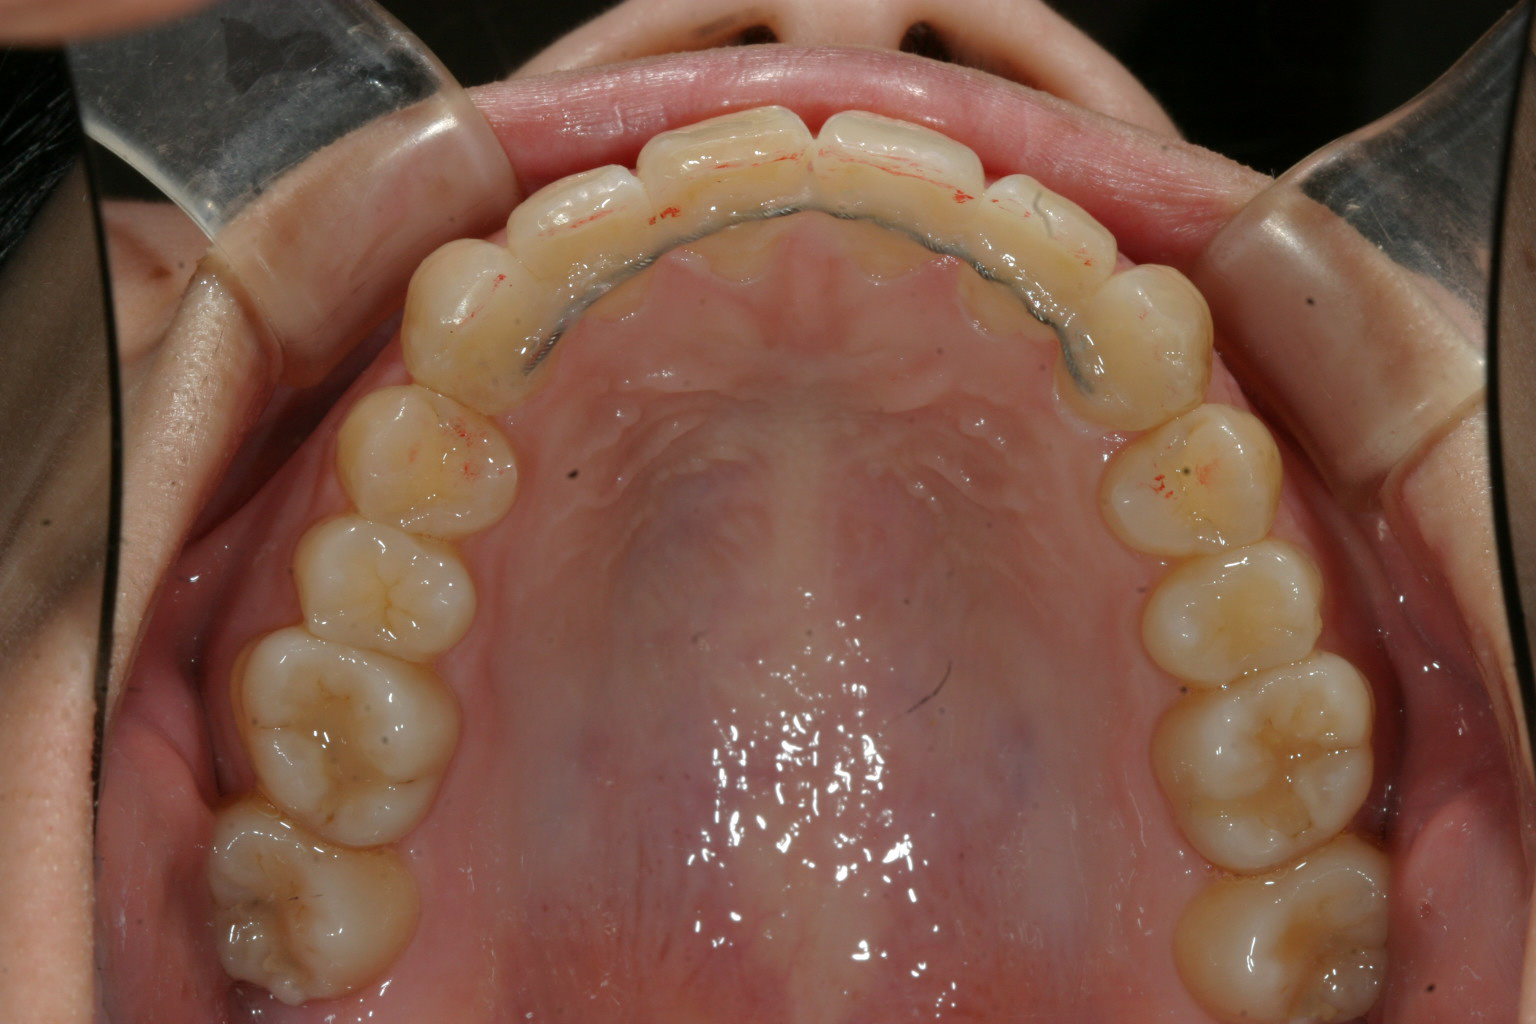

一歯だけ飛び出てるのが気になります。

下の前歯は歯列がV字形の為4本の前歯が上手く並ばずガタガタになってます。

こちらも歯列をU字形にする事により綺麗に改善してます。

こちらの症例は典型的な症例で歯列形が悪い為の不正咬合です。

これって言って特別何をしたって事無く歯列を V字形をU字形にするだけでここまで改善します。